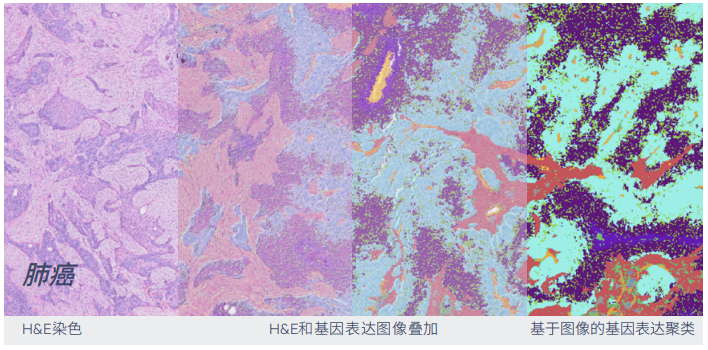

▲通过高分辨率的空间转录组学来增强 H & E 或 IF 成像后的样本。

▲兼容 H & E 染色以及 IF 染色 Visium HD 空间基因表达兼容 H &E 染色以及 IF 染色。

(可在同一组织切片上进行高分辨率空间转录组学数据分析)